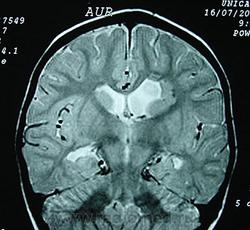

Гетеротопии. Перивентрикулярная гетеротопия. Субэпендимальная нодулярная (узелковая) гетеротопия.

Наиболее частым вариантом миграционных нарушений является гетеротопия - скопление нейронов, остановившихся в различных аномальных местах на пути следования к коре головного мозга. Такая остановка происходит не позже 5-го месяца внутриутробного развития. Изолированный участок узловатой массы называется «гетеротопион». В настоящее время описаны следующие варианты гетеротопии:

- субэпендимальная нодулярная (узелковая) гетеротопия;

Перивентрикулярная субэпендимальная гетеротопия